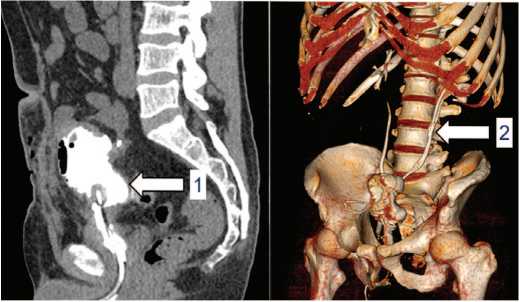

КТ мочевыводящих путей в динамике демонстри рует достаточную емкость артифициального мочевого пузыря, наличие стента в левом мочеточнике, восста новления адекватной уродинамики верхних мочевыво дящих путей (рис. 4).

Рис. 4. Больной Ж. КТ мочевыводящих путей с контрастным усилением после операции: 1 – увеличение емкости мочевого пузыря, 2 – внутренний стент в левом мочеточнике

Fig. 4. Patient J. Contrast-enhanced CT of the urinary tract after surgery: 1– increased bladder capacity, 2 – internal stent in the left ureter

Рис. 2. Пациент Ж. КТ мочевыводящих путей с контрастным усилением: 1 – левосторонняя калико-пиелоэктазия (лоханка до 21 мм, расширение шеек чашечек до 14 мм, чашечек до 24 мм), стриктура (сужение до 1 мм) нижней трети левого мочеточника, двухсторонняя уретероэктазия, более выраженная слева; 2 – микроцистис, утолщение стенок мочевого пузыря до 12 мм

Fig. 2. Parient J. Contrast-enhanced CT of the urinary tract: 1- left-sided hydronephrosis (ureter up to 21 mm, dilatation of the calyces up to 14 mm and the calyces up to 24 mm), stricture (narrowing to 1 mm) of the lower third of the left ureter, and bilateral ureteroectasia, more pronounced on the lef; 2 - microcystis, thickening of the bladder walls up to 12 mm